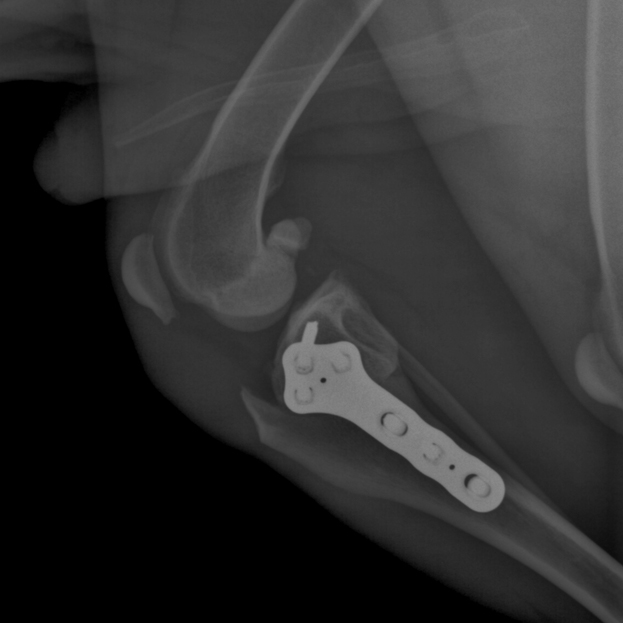

Tibial Plateau Leveling Osteotomy

This course is designed for veterinarians who want to specialize in orthopedic surgery and want to learn advanced techniques for managing knee injuries in small animals.